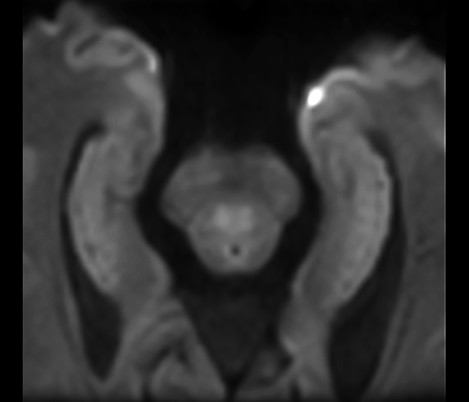

Casos clínicos de praticamente todas as anatomias Explore mais de 100 casos clínicos dos seus colegas do mundo inteiro, que demonstram como a tecnologia de RM digital da Philips fortalece os seus recursos de diagnóstico por imagem.